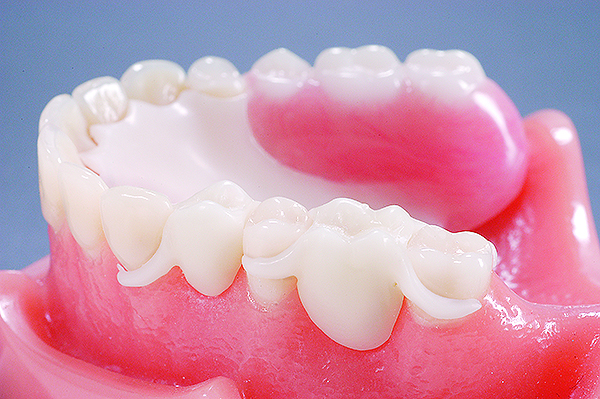

The primary application for this material has been for RPD frameworks (Figure 1).

Fig 1. Removable partial denture framework fabricated using acetal resin.

Figure 1